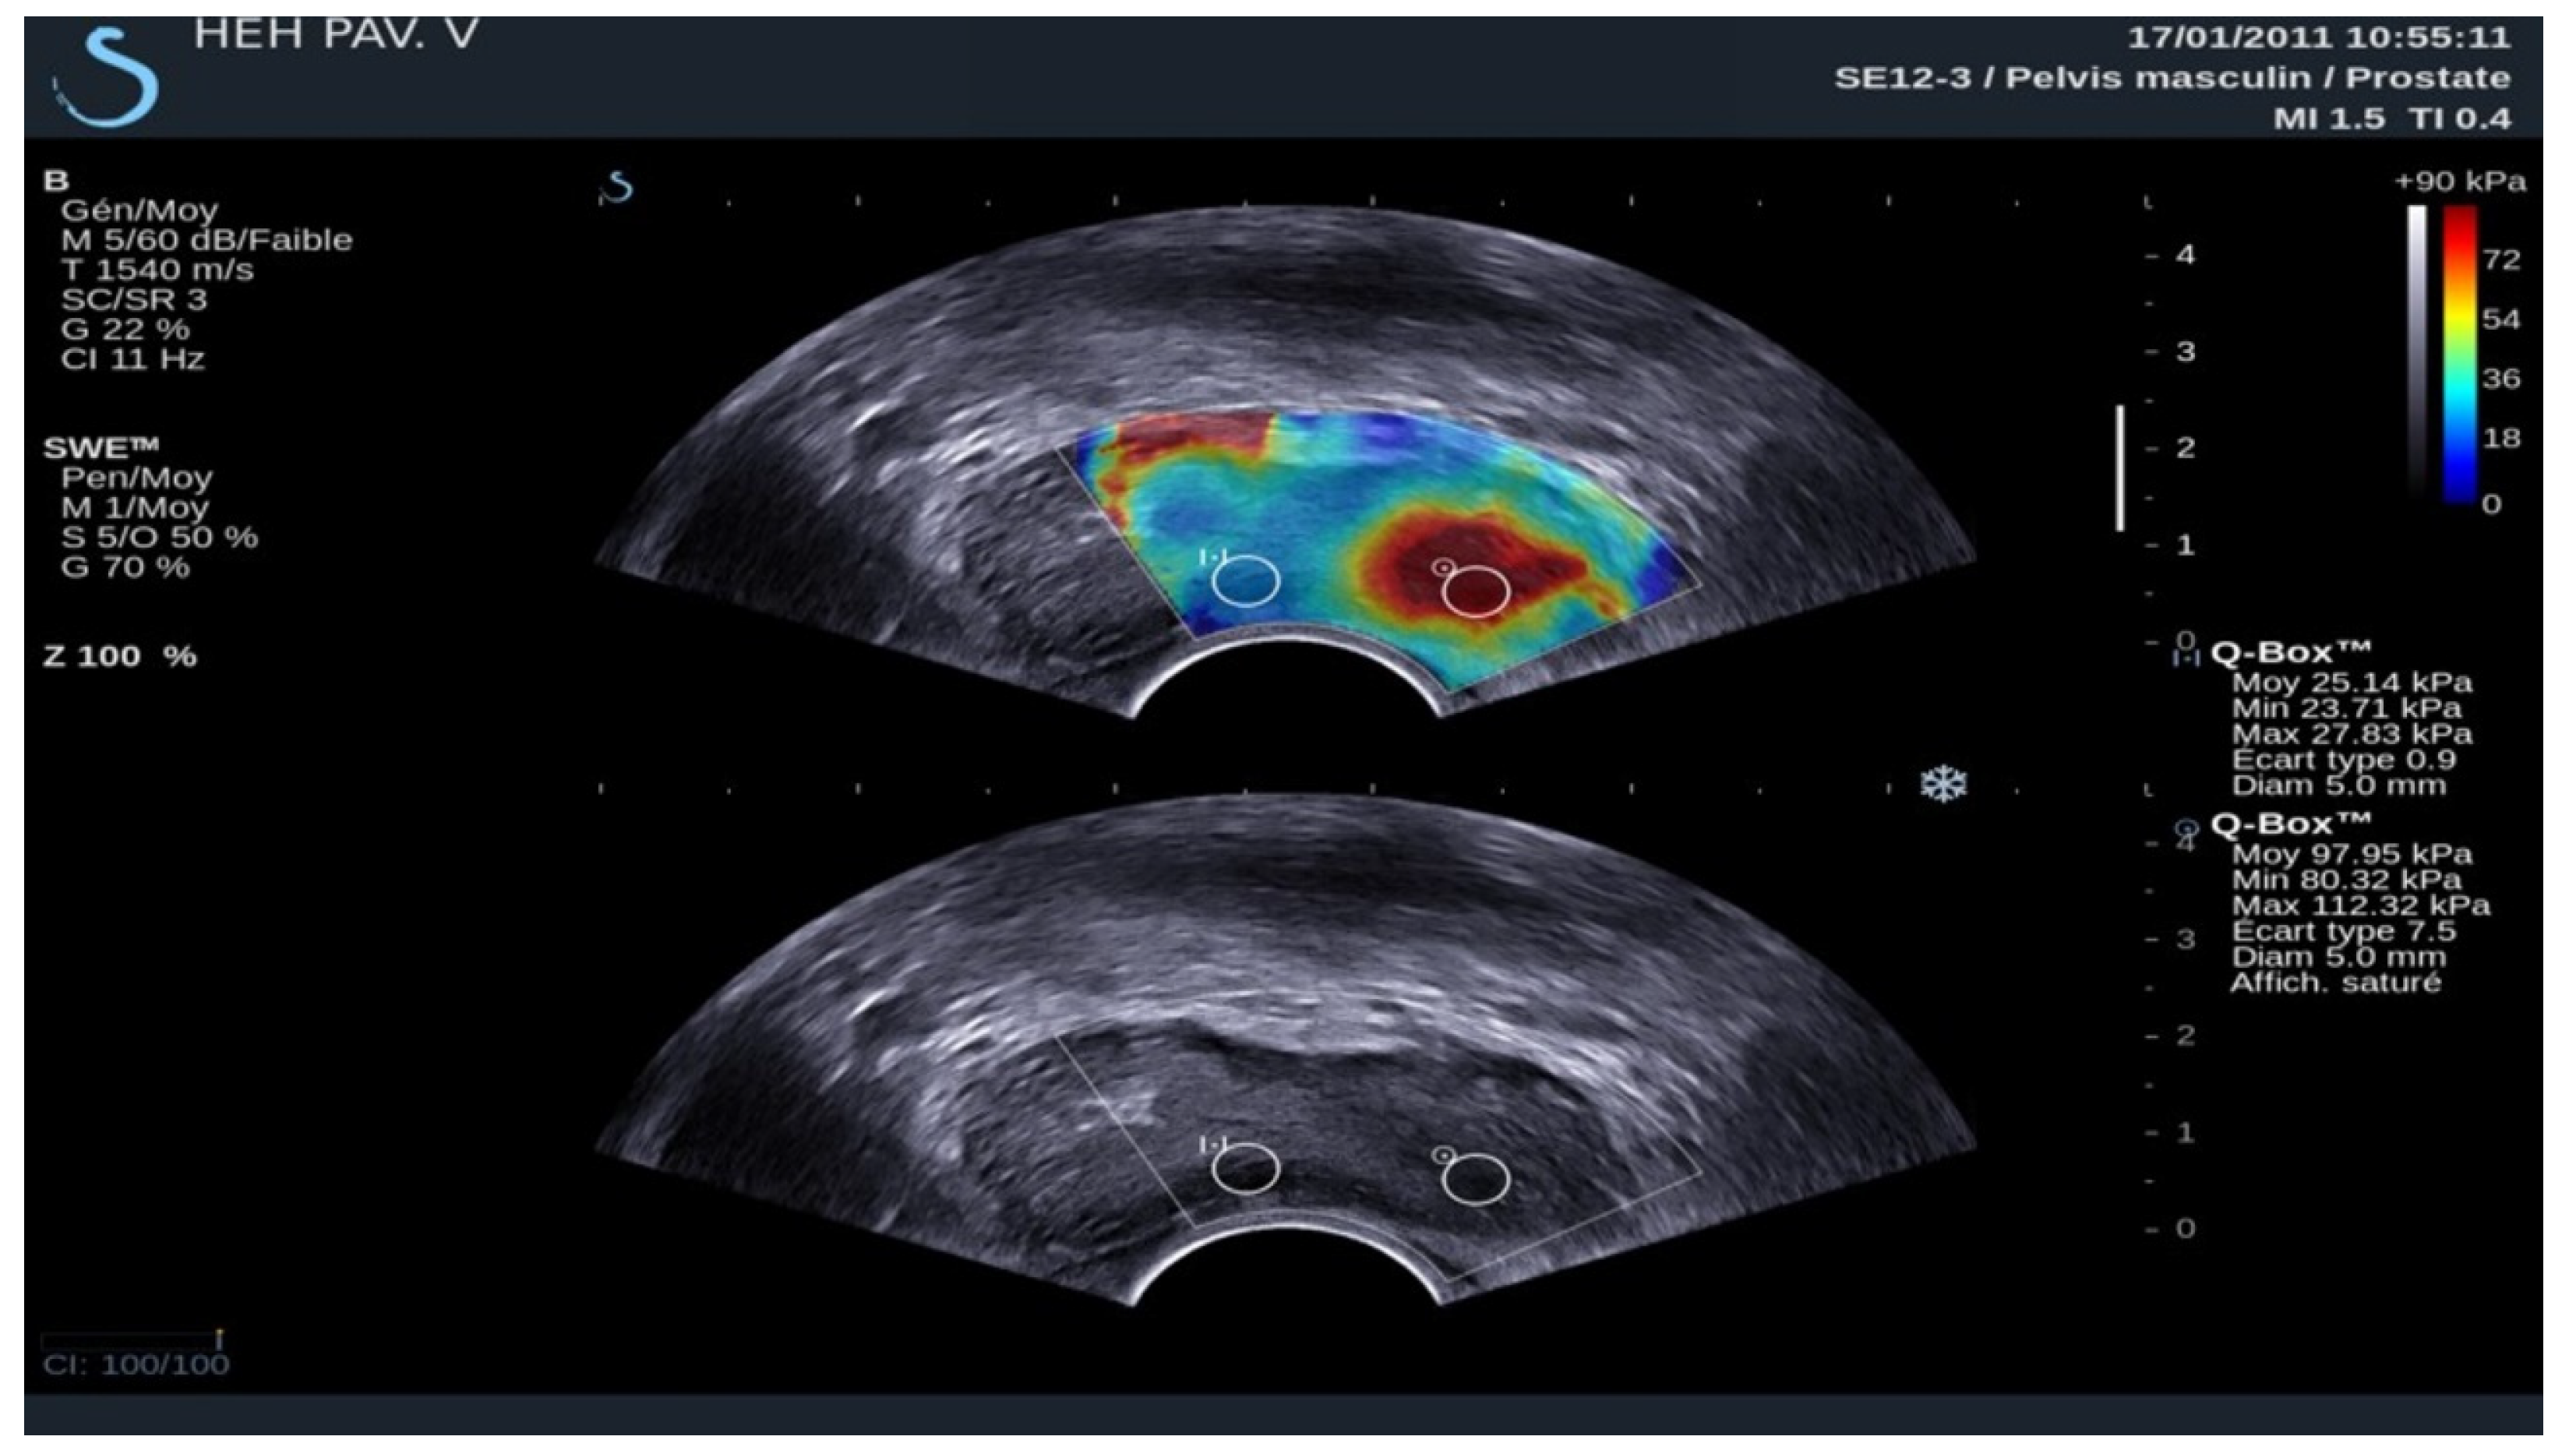

3.3. Elastography in Prostate Lesions

- Correas, J.M.; Tissier, A.M.; Khairoune, A.; Khoury, G.; Eiss, D.; Hélénon, O. Ultrasound elastography of the prostate: State of the art. Diagn. Interv. Imaging 2013, 94, 551–560. [Google Scholar] [CrossRef] [PubMed]

- Dai, W.B.; Xu, J.; Yu, B.; Chen, L.; Chen, Y.; Zhan, J. Correlation of Stiffness of Prostate Cancer Measured by Shear Wave Elastography with Grade Group: A Preliminary Study. Ultrasound Med. Biol. 2021, 47, 288–295. [Google Scholar] [CrossRef]